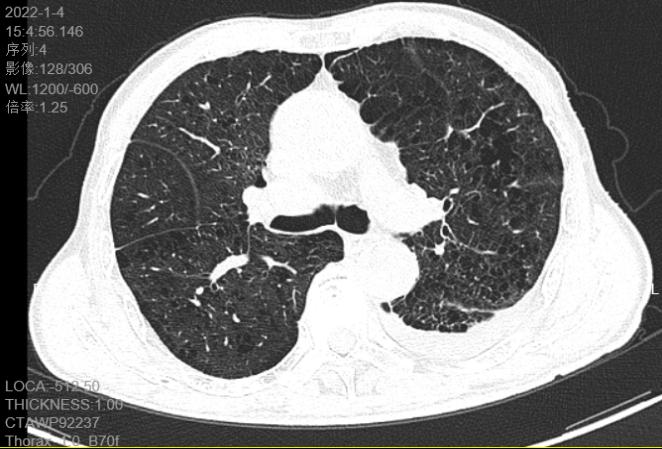

治疗后患者左肺已复张

后面几天,黄伯胸管连接水封瓶内的气泡逐渐减少,复查胸部CT左肺已经复张,2022年1月5日顺利拔出引流管,观察两天无不适后顺利出院。出院时黄伯对呼吸内科的医护竖起了大拇指!